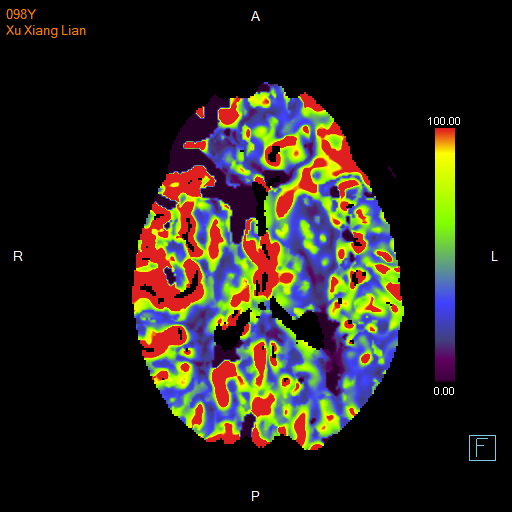

进一步的血管检查(CTA+CTP)发现了更严重的问题:王奶奶的左侧颈内动脉完全闭塞——这是脑梗中最凶险的类型之一,意味着大脑主要供血通道被切断,随时可能危及生命

颅脑 CTP